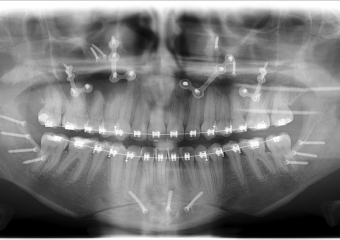

Rx panorâmico apos a cirurgia